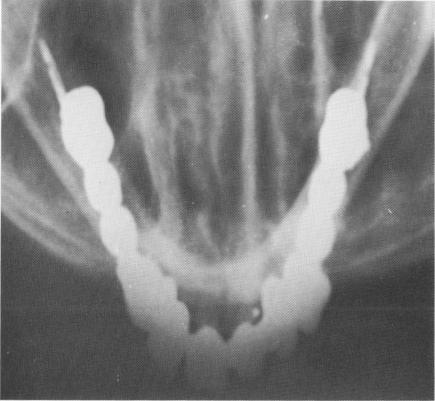

Fig. 11-18. This radiograph clearly shows the suitability of the blade implant for knife-edge ridges.

2 X ray shows suitability of dental blade implant for knife edge ridges